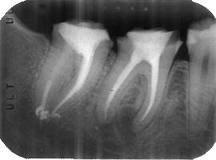

7. Conometría

7- Conometria:

Consiste en introducir un cono maestro del tamaño a la ultima lima usada, para observar el ajuste al conducto en la región apical. El cono debe quedar a 0,5 mm del limite radiográfico apical.

Nota: Los cono que adquirimos en el comercio suelen no estar estandarizados y por ello no suelen ajustar en la zona apical. Hoy en el mercado hay conos con conicidades especiales que están estandarizados y por lo general suelen ajustar muy bien en la región apical; pero las limas que debe utilizar también tienen una conicidad especial. Ver Protaper Universal y Mtwo